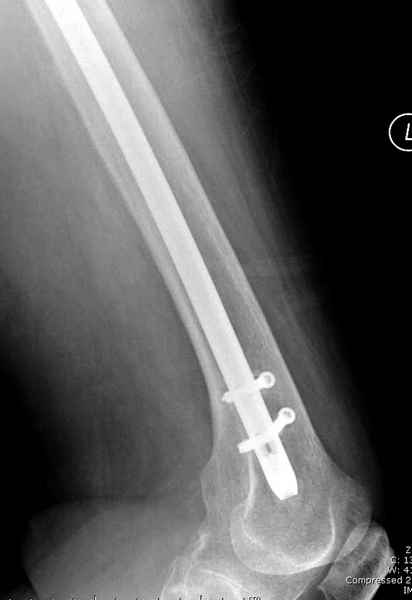

Михаил, здравствуйте. Если присмотреться - на четвертом снимке есть перелом гвоздя по отверстию.

Видимо, проблем тут две: во-1-х, центральный отломок был оставлен в варусно-сгибательной установке, во-2-х, не динамизировали вовремя.

Нижние винты хотели сломаться, но, увы, один не сломался, и тогда сломался гвоздь. Хотя и при динамизации в таком положении отломков

могло не срастись.

Не стали усложнять интрамедуллярным вариантом коррекции, легче контролировать коррекцию пластиной, поэтому сделали операцию 95 градусной Blade Plate, разогнув до 110 градусов.

Надеемся на успех, потому что до введения пластины дефект от импланта забили костной стружкой и удалось создать компрессию между отломками, максимальную для импланта (150 кило/паунд). Сделана дополнительная костная пластика и за счет измененного угла пластины устранено укорочение конечности.